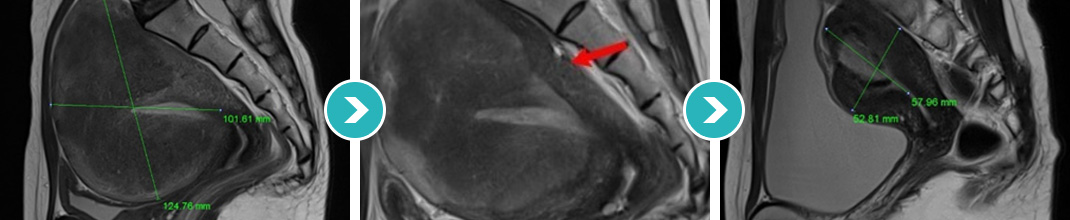

8cm 크기 자궁후벽과 저부 자궁선근증 하이푸 치료후 90%이상 치료, 42개월 장기 추적관찰